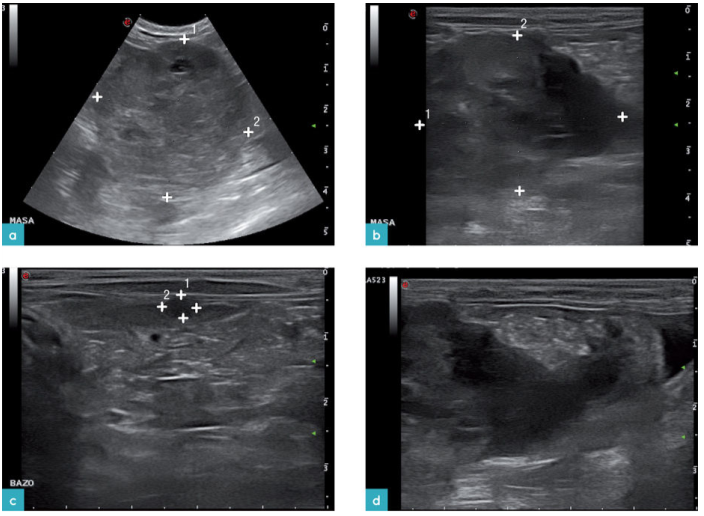

对27只患有脾脏肥大细胞瘤的猫进行研究,观察这些猫的脾脏影像,发现与患有淋巴瘤的病变影像相似。在这些病例中,93%的猫都有不同程度的脾脏肿大,其中有6只猫唯一的异常表现就是脾脏肿大。在2只缺乏典型症状的猫的检查中仅发现有脾脏增大,且有多处高回声的结节。其中1只猫的脾脏呈广泛性高回声,同时伴有脾脏肿大。在其中7只猫的脾脏上发现有单独的结节或肿块(图10.图4)。30%的猫同时伴有肝脏的变化。33%的猫有腹膜腔积液。

患有内脏型肥大细胞瘤的猫,它的副肿瘤综合征表现为胸膜腔和腹膜腔的渗出液中含有嗜酸性粒细胞,同时外周血中也含有较多的嗜酸性粒细胞。然而,这项研究没有发现能够区分肥大细胞瘤和淋巴瘤的超声特征。但是通过这项研究发现,患有淋巴瘤的猫发生腹腔积液的概率比肥大细胞的患猫高(47%比33%),发生肠系膜或腹膜后淋巴结病变概率也比肥大细胞的患猫高(37%比3%)。肥大细胞瘤的患猫脾脏的轮廓则更为不规则,并且高回声病灶仅见于肥大细胞瘤的患猫。这表明小型的高回声结节或弥漫性高回声结节虽是比较少见,但如果发生,可以作为猫脾脏肥大细胞瘤的特异性影像。

内脏血管肉瘤在猫中并不常见,并且通常为多灶性,其中约23%的病例可见脾脏实质内有多处局灶性病灶。病灶表现为低回声或混合回声,或无回声,并伴有腹腔积液(图11)。